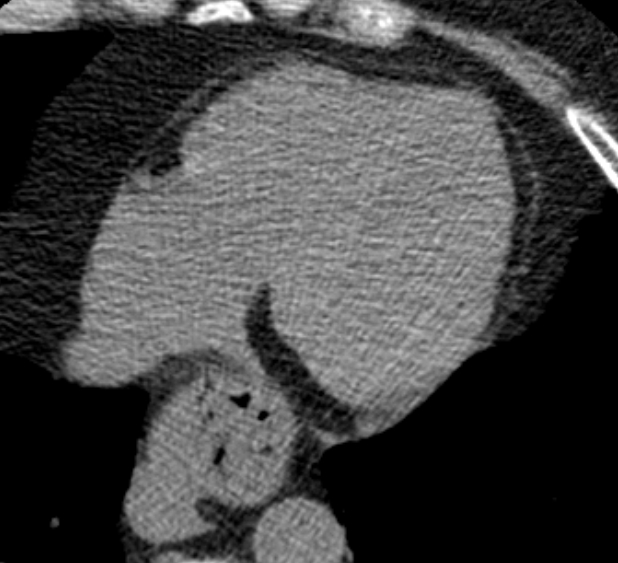

В нашей клинике исследование выполняется на новейшем 128-срезовом мультиспиральном компьютерном томографе экспертного класса TOSHIBA AQUILION CXL. Объектом данного исследования является сердце и коронарные артерии. Томограф производит послойное сканирование области сердца с шагом от 0,5 мм, и, благодаря высокой плотности отложения кальция и кальцинированные бляшки хорошо видны на снимках. За счет увеличенного количества сверхчувствительных детекторов сканирование происходит за несколько секунд, при этом доза рентгеновского облучения для пациента минимальна.

Для большей наглядности и определения точной локализации кальцинатов полученные при сканировании данные преобразуются аппаратом в объемные изображения сердца и сосудов.

Затем на основании полученных данных вычисляется индекс коронарного кальция (индекс Агатстона) для каждого коронарного сосуда в отдельности. Отсутствие кальция говорит о низком риске сердечно-сосудистых заболеваний.

Высокие показатели индекса кальция свидетельствуют о явном атеросклеротическом поражении коронарных артерий и образовании кальцинированных бляшек.